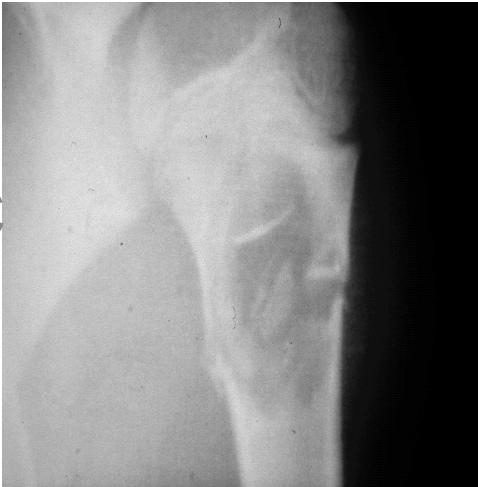

site: distal femur size: Most (involving how much? / cm?) matrix: mixed - mainly radiopaque , wide zone of transition, cortical destruction, resulted periosteal reaction, and codman’s triangle soft tissue involvement: